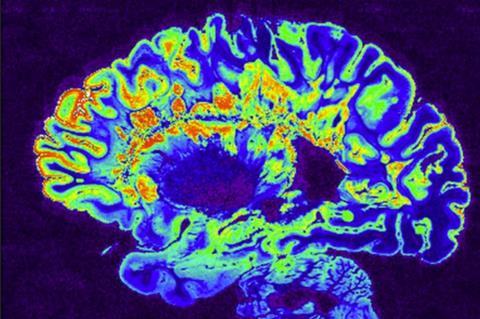

Long before written history, our ancestors encountered viruses that left permanent marks in the human genome. These relics, called endogenous retroviruses (ERVs), now make up an estimated 8% of human DNA. Far from being inactive fossils, some of these viral sequences continue to affect biology—sometimes in surprising or even vital ways. Explore twelve ancient viruses that have withstood millions of years, and learn what their hidden legacies mean for humanity.

Ancient viral sequences, known as endogenous retroviruses (ERVs), have not only shaped our evolutionary history but continue to play active roles in our biology. (en.wikipedia.org) These remnants, comprising about 8% of the human genome, influence various physiological processes, including gene regulation, immune responses, and development. (pubmed.ncbi.nlm.nih.gov) Ongoing research aims to elucidate whether these elements act as beneficial contributors or potential contributors to diseases such as cancer and autoimmune disorders. (pubmed.ncbi.nlm.nih.gov) As genomic studies advance, a clearer understanding will emerge of how these ancient invaders, now integral to our DNA, might even contribute to future medical advancements. (pubmed.ncbi.nlm.nih.gov)